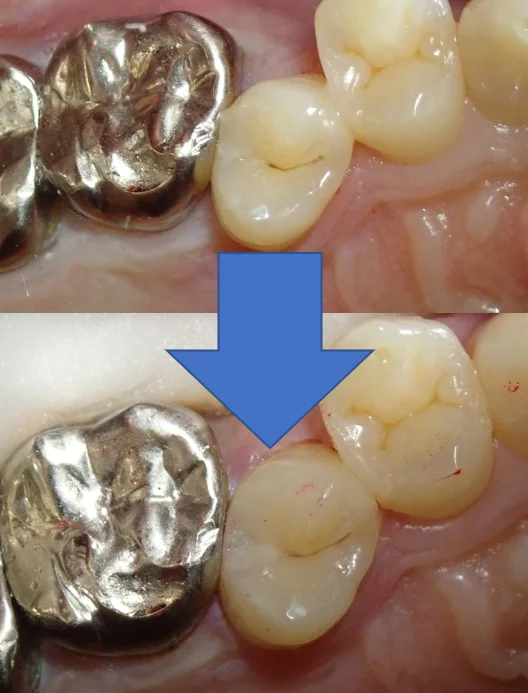

で、2日目最終的な術前術後がこちらです。

歯の乾燥の為、まだ色が合っていませんが、1週間くらいすると馴染んできます。

無事に虫歯も取りきり、段差などなく仕上げることが出来たため、良かったです。